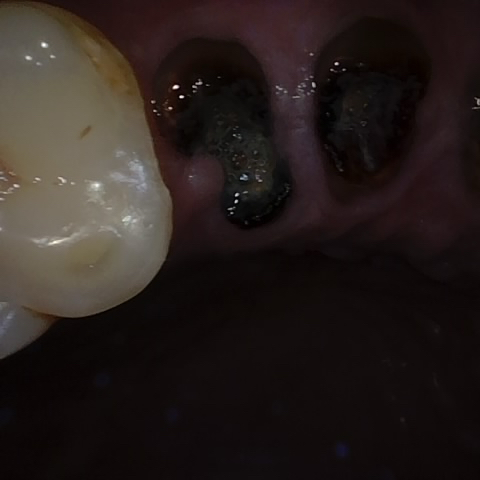

Incorrect Quality Level

The reference annotation for this image is

None

.

Please select the correct quality level.

Annotated as "Good"